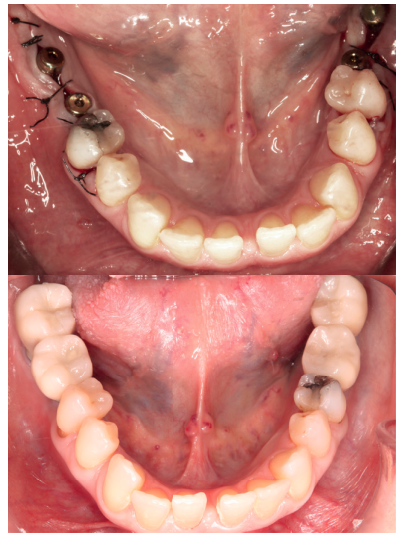

Paciente mujer de 55 años que acude a la consulta para rehabilitar protésicamente sectores posteriores (Figura 1). A nivel oral presenta patología dental y periodontal además de las ausencias de molares. Con necesidad de tratamiento quirúrgico, periodontal y restaurador (Figura 2).

A nivel odontológico el diagnóstico y el tratamiento de la paciente presenta patología dental y periodontal además de las ausencias dentarias. Se realizaron obturaciones, tratamiento periodontal básico y quirúrgico, extracciones dentarias, rehabilitación con prótesis fija y tratamiento rehabilitador con implantes dentales (Figura 3).